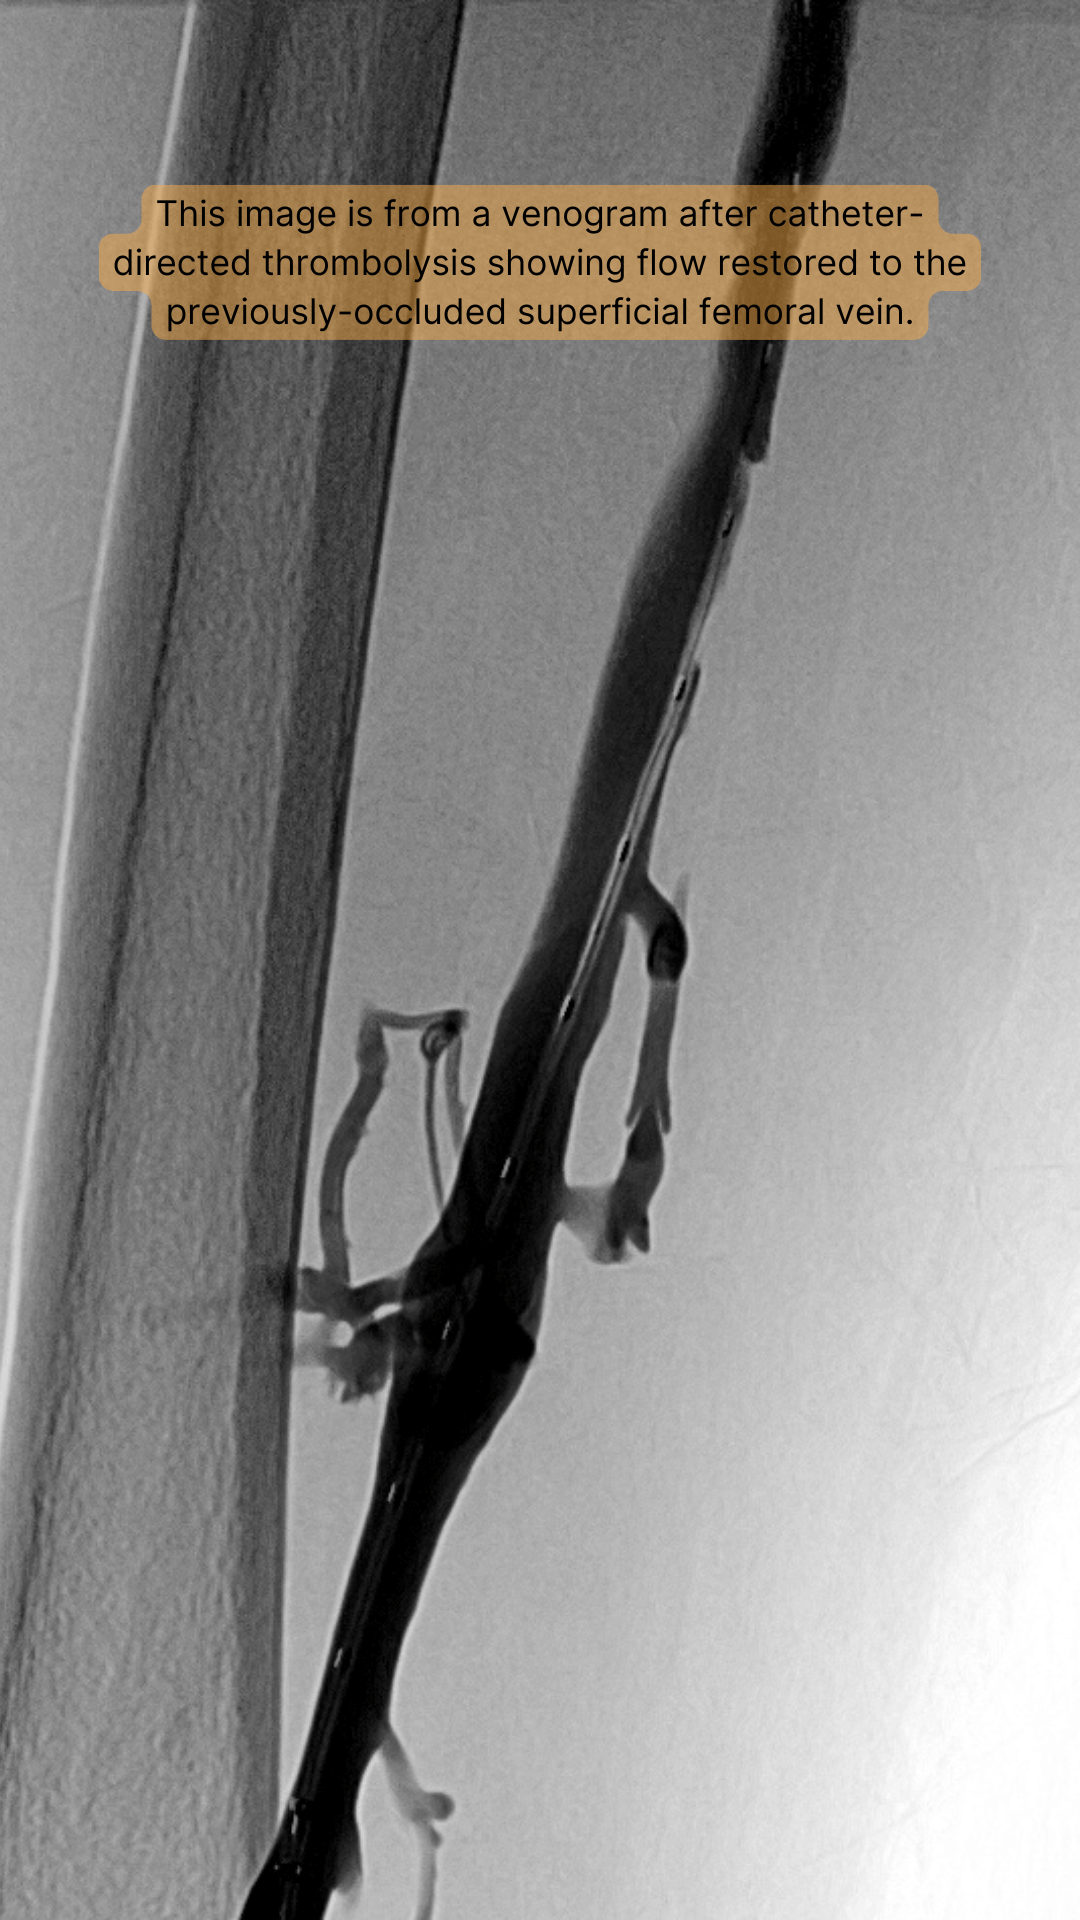

Catheter-directed thrombolysis is performed by an interventional radiologist and is best performed as soon as possible after a DVT is diagnosed. Prior to the procedure, some patients may receive a CT scan of the head to make sure that there is not an increased risk for bleeding. During this procedure, a small catheter (tube) is placed directly into the affected vein, usually from behind the knee. Once the catheter is in place, a drug can be administered directly into the clot in order to dissolve the clot. New devices are now available which can disrupt the clot in order to facilitate delivery of the drug directly into the thrombus. These devices also allow for the removal of the clot through the catheter. By removing the clot, it is hoped there will be less damage to the vein and therefore fewer symptoms associated with a post-thrombotic syndrome. Once the clot is dissolved and/or removed, it may be possible to see if there is any narrowing within the vein. This can subsequently be treated with angioplasty or placement of a stent within the narrowed vein. Often patients need to spend the night in the intensive care unit (ICU) while the drug to dissolve clot is being given.

There are several studies that have evaluated outcomes after the endovascular treatment of DVT. It has been shown that 90% of patients can be treated successfully, meaning that flow in the vein is restored and symptoms are improved (Oklu R and Wicky S, 2013) In general, these studies have shown documented patency rates of up to 75-85% at 1 year (Amin VB and Lookstein RA, 2014). In addition, catheter-directed treatment of DVT has been shown to improve quality of life and reduce the incidence of post-thrombotic syndrome (Comerota AJ, et al, 2000).